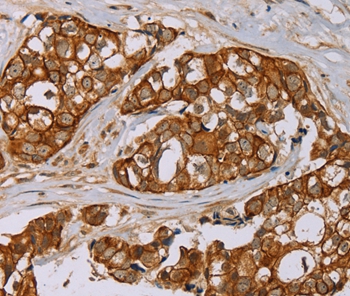

Immunohistochemical analysis of paraffin-embedded Human thyroid cancer tissue using #36626 at dilution 1/40.

Immunohistochemical analysis of paraffin-embedded Human breast cancer tissue using #36626 at dilution 1/40.